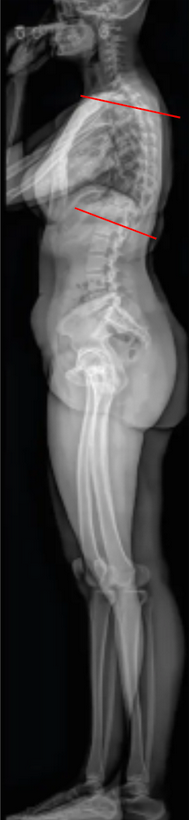

Thoracic Kyphosis (T5–T12 Cobb)

Thoracic Kyphosis (T5–T12 Cobb Angle) quantifies the posterior convex curvature of the thoracic spine in the sagittal plane.

• Obtain a standing lateral full-length spine X-ray, ensuring visualization from C7 through the sacrum.

• Identify the superior endplate of T5 and the inferior endplate of T12:

• If the endplates are difficult to visualize, select the closest clearly defined adjacent vertebrae (T4/T11).

• Draw a straight line along the superior endplate of T5.

• Draw another line along the inferior endplate of T12.

• Construct perpendiculars to each of these lines and measure the angle formed at their intersection — this is the T5–T12 Cobb Angle, representing thoracic kyphosis.

• The angle opens posteriorly (convexity backward).